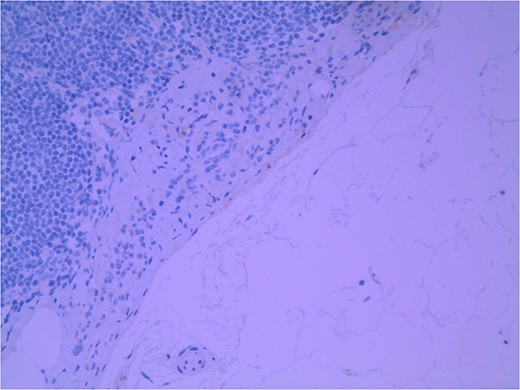

Lymph node specimens were sent for haematoxylin and eosin (H&E) staining (Fig. 3) and IHC analysis. The sections showed mild reactive changes and benign intracapsular nevoid rests. IHC analysis showed that these cells were negative for HMB-45 (Fig. 4) and were positive for both Sox10 and p16 (Figs 5 and 6). Consensus at the Multidisciplinary Team Meeting was that the appearance was in keeping with benign naevoid rests as opposed to melanoma deposits, given the location of the cells, morphology and immunohistochemistry. Surveillance was recommended.

Lymph node with IHC using Sox 10 stain, staining melanocytic cells (benign or malignant) in subcapsular region; × 200 magnification.

Several IHC stains are in use in the pathological interpretation of primary lesions and SLN biopsies. The antibody HMB-45 reacts with most melanomas. In a primary lesion, HMB-45 is immunoreactive with intraepidermal and superficial dermal components of benign nevi [14]. In a lymph node, however, benign nevoid cells are negative for HMB-45 and appear bland. A loss of HMB-45 expression has been reported in 20% of melanocytic metastasis, illustrating the need for further diagnostic testing [14]. Sox10 is a nuclear transcription factor that stains benign and malignant melanocytic cells. It indicates the extent of melanocytic spread but does not differentiate between benign nevi and metastatic melanoma [15]. Immunostaining for the tumour suppressor gene p16 differentiates between benign naevi and melanocytic metastases in the SLN. One study demonstrated positive nuclear and cytoplasmic p16 staining in all nevi (dermal and lymph node) and the absence of nuclear p16 staining in all but one melanoma metastasis [14]. No single stain is completely sensitive for melanocytic metastases, and a confident diagnosis relies upon cell location, morphology and multiple IHC techniques. SLN biopsy in the current patient demonstrated intracapsular melanocytic cells which stained negative for HMB-45, and positive for Sox10 and p16, in keeping with benign nevoid rests as opposed to metastatic melanoma.